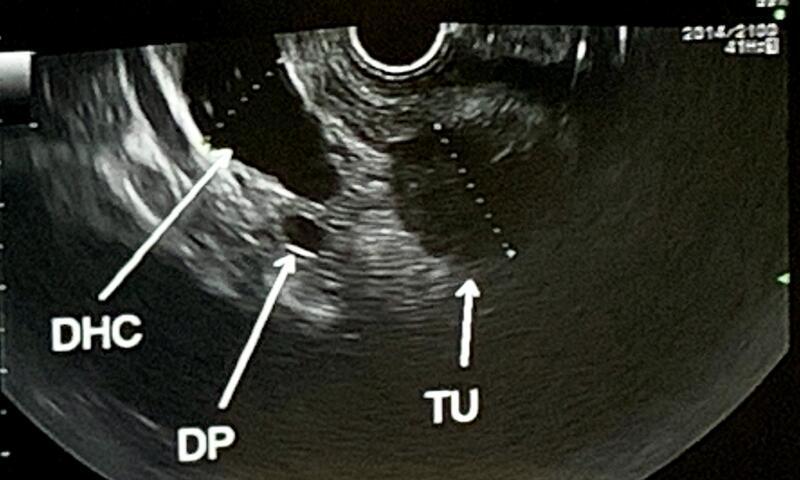

• Gallenwege/Gallestau: Ursachenklärung, z. B. kleine Steine oder Engstellen (EUS kann Gallengangssteine sehr zuverlässig erkennen/ ausschliessen).

• Tumorabklärung & Stadieneinteilung (Staging): Speiseröhre, Magen, Pankreas, Mastdarm – inkl. Beurteilung von Lymphknoten.

EUS liefert sehr detailreiche Bilder, weil der Ultraschall von innen und damit sehr nahe am Organ erfolgt – besonders hilfreich bei Pankreas/Gallenwegen und Lymphknoten.